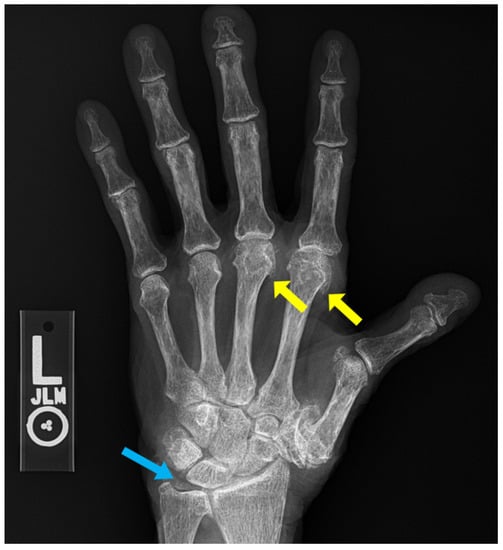

7. Calcium Pyrophosphate Dehydrate Arthropathy (CPPD)

8. Gout